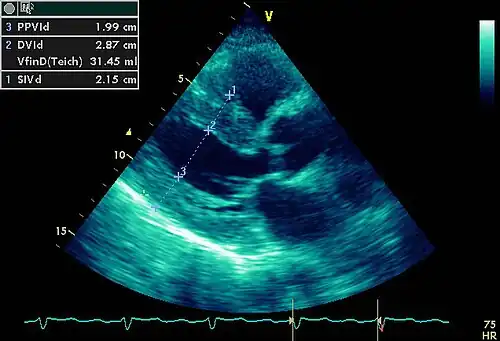

- Ecocardiograma dóppler-color. Estudio no invasivo de altísimo rendimiento diagnóstico. No es un estudio de primer nivel porque requiere de equipo sofisticado y personal altamente entrenado, por lo que su costo es relativamente alto. No se recomienda la ecocardiografía de rutina en pacientes con hipertensión sin síntomas o evidencia clínica de daño orgánico cardíaco.